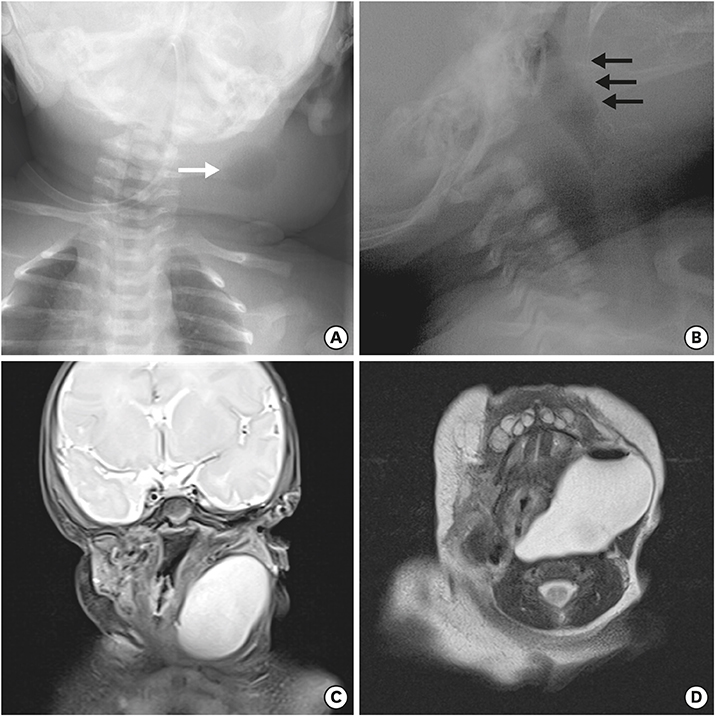

A newborn female infant, gestational age of 39+2 weeks, and 3.46 kg at birth was referred to our NICU due to a 7 cm sized left neck mass presented at birth. No significant medical history during antenatal care was noted. The baby arrived at our NICU 3 hours after birth and physical examination revealed a soft, tense, movable 7 cm long mass without signs of inflammation. Initial neck X-ray showed a 4.7×3.9 cm sized soft tissue density mass at left side of the neck containing round air density (Fig. 3A). With experience of patients with pyriform sinus cysts, gastric tube feeding was initiated from day 1. A sonographic study of the neck mass revealed findings consistent with pyriform sinus cyst, located at the medial side of the left carotid artery and extending to the posterior aspect of the left thyroid gland. The cyst was unilocular and contained isoechogenic debris. Esophagography showed a small tubular opacity from the left pyriform sinus adjacent to the air-filled cyst, suggesting a fistula (Fig. 3B). On neck magnetic resonance imaging (MRI), the fistula was not visualized but a cyst of homogeneous signal intensity without wall thickening or enhancement was visualized with air-fluid level, suggesting communication with the esophagus (Fig. 3C and D). On the 6th day of admission, pyriform sinus cyst resection and fistula ligation was done (Fig. 4). The size of the cyst was 7.0×3.5 cm on operation findings. Histological results of the dissected cyst were negative for malignancy and showed many benign squamous epithelial cells with some multinucleated histiocytes and mixed inflammatory cells. There was no intra-operative complication and the patient recovered uneventfully. Bottle feeding was initiated on postoperative day 7 and the patient was discharged 10 days after surgery.

Fig. 3

(A) Neck anteroposterior view and (C, D) T2-weighted neck magnetic resonance imaging of cystic mass with air (white arrow). (B) Fistulography shows a faintly opacified hairline tract (black arrows) originating from the left pyriform sinus.

Air bubbles in the inflammatory cavity of pyriform sinus tract may be due to production of air-forming bacilli or inhaled air from opening of pyriform sinus tracts [6]. These air bubbles may be noted on US, CT or MRI findings, and also on close observation of initial plain X-rays. In our first case, air bubble was not found on US but was visualized on the neck CT. At first, we assumed it to be air-fluid level within an abscess formed by anaerobic bacterial infection and treatment was targeted toward infection based on the assumption of complicated infected cystic hygroma. Earlier acknowledgement of the possibility of air inflow from an open sinus tract would have accelerated the process of correct diagnosis.